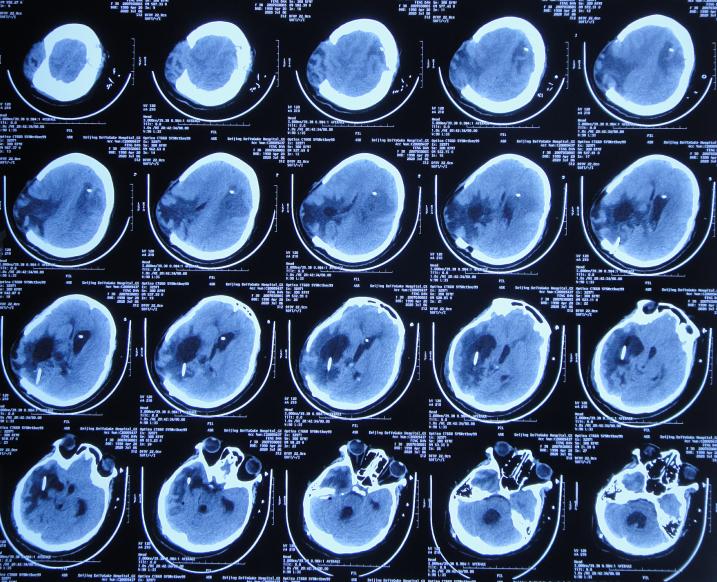

入院次日即2020年7月6日,进行了颞角外引流术,术后当天复查头颅CT示脑室内有2根管( 图-18 ), 脑脊液细菌培养示肺炎克雷伯菌(仍是外院开颅术后14天时查出的细菌,说明之前的细菌一直并未彻底消灭)。

图-18: 2020年7月6日头颅CT